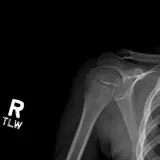

MSK Radiographs

Chest Radiographs